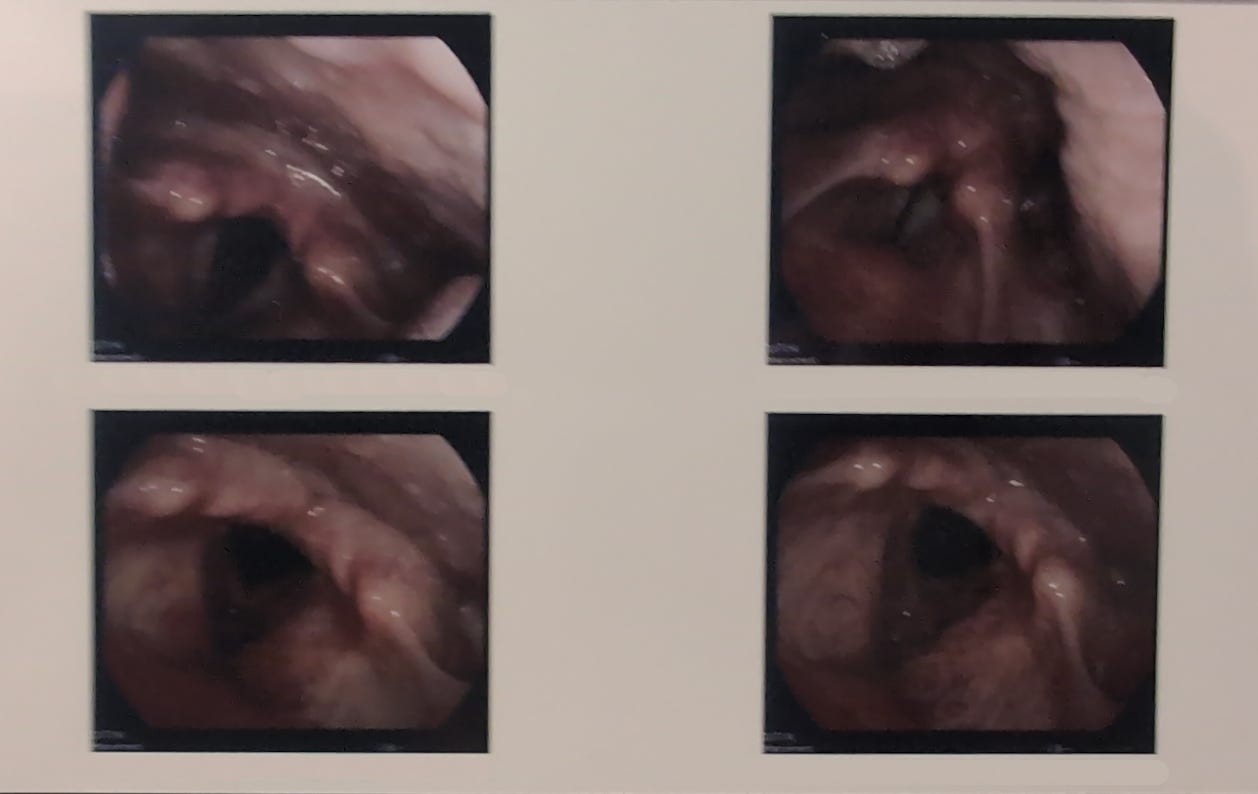

I went and saw Dr. Kim again. He looked at my vocal cords and said they look fine still, and took another pic of my vocal folds.

Can I get pictures of my vocal folds?

And she said yeah. You can see these later.

They printed out the pictures of the vocal cords for me again.

Pictures of my vocal folds before